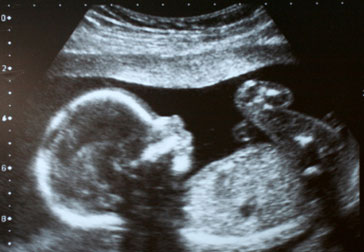

Второй скрининг: узи на 22 неделе беременности

В «интересном положении» для женщины новый день всегда не похож на предыдущий. Чтобы контролировать все этапы планомерного внутриутробного развития, предусмотрено три обязательных скрининга, которые...